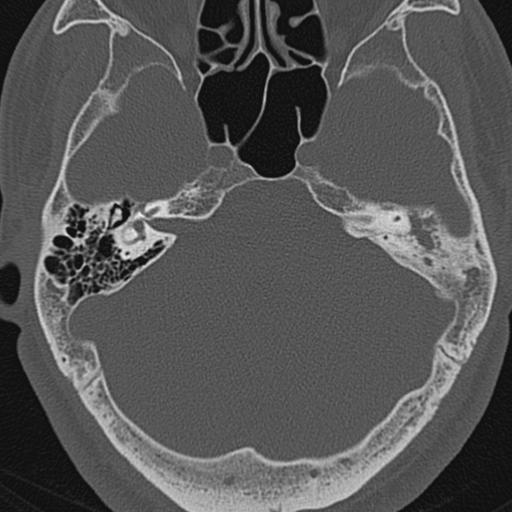

以下是引用zxl51642在2009-8-25 13:37:00的发言:[br]1、左侧慢性硬化型中耳乳突炎(中耳鼓室腔及听小骨受累),并胆脂瘤形成;2、左侧外耳道软组织密度影填塞,考虑炎性肉芽肿,建议结合临床;3、右侧颈静脉窝较左侧明显扩大,不排除颈静脉球瘤,建议mr进一步检查。

以下是引用随光逐影在2009-8-25 19:05:00的发言:[br]1)左侧慢性中耳乳突炎(肉芽肿或胆脂瘤形成),左侧外耳道炎性肉芽肿。2)右侧颈静脉球高位。